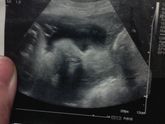

Как считаете, пойдет такой конверт на осень? Пдр на 8 октября ставят